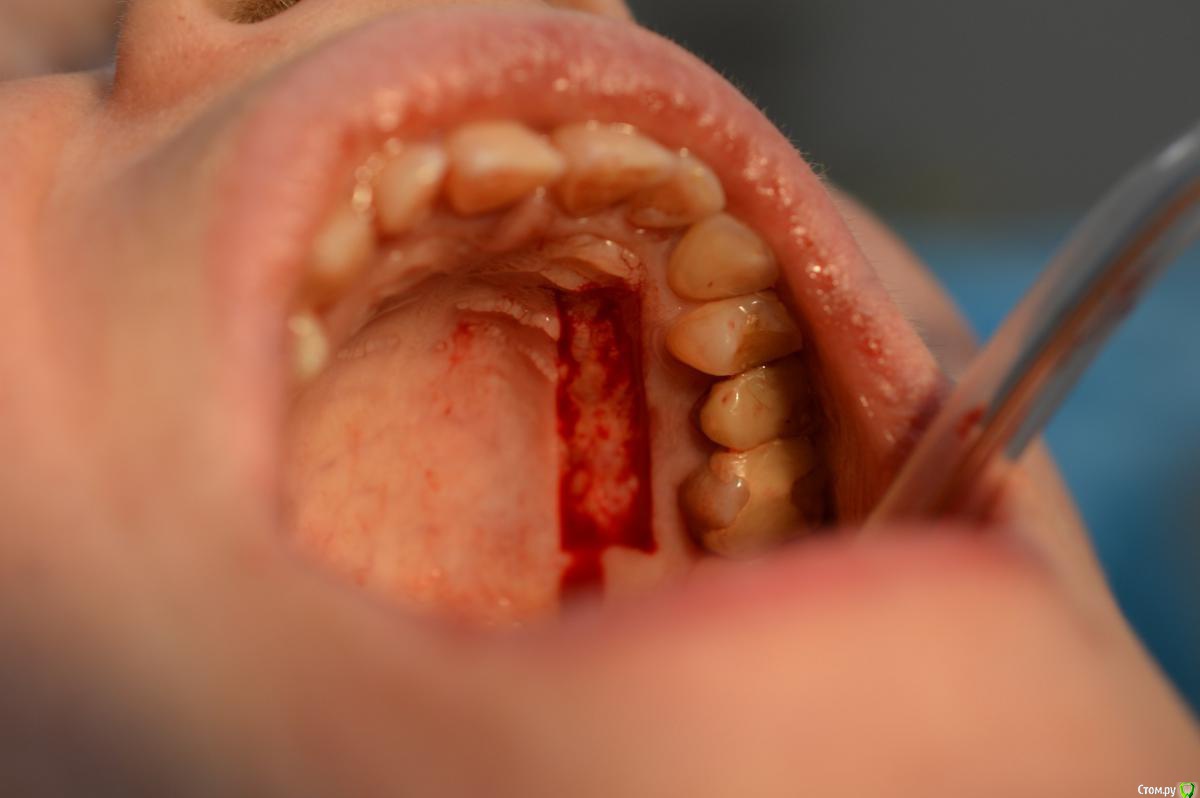

Dr.Safiullin Опубликовано 12 мая, 2017 Поделиться Опубликовано 12 мая, 2017 (изменено) Добрый вечер всем, решил тоже свой первый, небольшой кейс выложитьСильно не ругайте, полгода как получил диплом) Вопрос: 1)Нужно ли подшивать губу? Я не подшил, потому что в гос. времени мало на приём, да и испугался надкостницу травмировать лишний раз. А то боялся получить рубец, хотя не получил его!) 2) на 5 фотке это десквамация? Приветствуются конструктивная критика! Спасибо Изменено 12 мая, 2017 пользователем Dr.Safiullin Ссылка на комментарий

Dr.Safiullin Опубликовано 13 мая, 2017 Автор Поделиться Опубликовано 13 мая, 2017 Доктор, вы прекрасно провели ненужную и бесполезную операцию )) Тут не было показаний для вестибулопластики.Может быть, но а как же преддверие 1.5-2мм, тонкий биотип десны, рецессия по 3 классу по Миллеру в области фронтальных зубов? Из за скученность тоже убыль, но все же. Вот тут может быть информативнее будет Ссылка на комментарий

колесников Опубликовано 13 мая, 2017 Поделиться Опубликовано 13 мая, 2017 (изменено) Прелестное было преддверие. Обратить внимание следовало на особенности прикуса, выявить в анамнезе бруксизм, местно -суперконтакты. Думаю причина рецессии в перегрузке.Кстати подшивать лоскут надо было к кератинизированой слизистой,тогда не было бы диссонанса в цвете в виде зебры ,в окончательном варианте Изменено 13 мая, 2017 пользователем колесников Ссылка на комментарий